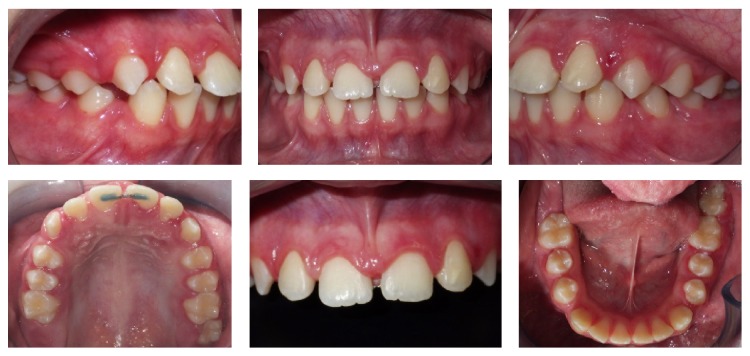

2.4. Treatment Results

The treatment promoted a reduction in the diastema to a size that was similar to the physiological “ugly duckling” phase. The maxillary left central and lateral incisors were moved mesially to a greater extent than the maxillary right central incisor to match the midline. The appliance was removed, and a flat wire segment was bonded into the palatal surfaces of both central incisors with the intention of being maintained until complete eruption of the canines (Figures 4 and 5).

Figure 4.

Posttreatment intraoral photographs.

Figure 5.

Posttreatment radiographs and cephalometric measurements.